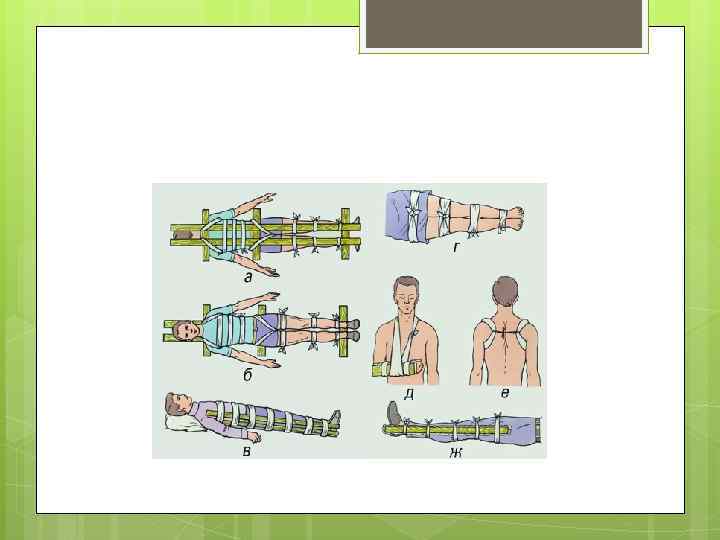

Основная цель иммобилизации Достижение неподвижности костей в месте перелома. При этом yменьшаются боли, что способствует предупреждению травматического шока. Приемы проведения иммобилизации должны быть щадящими. Неподвижность в месте перелома обеспечивают наложением специальных шин или подручными средствами путем фиксации двух близлежащих суставов (выше и ниже места перелома). Такая иммобилизация называется транспортной.

Основная цель иммобилизации Достижение неподвижности костей в месте перелома. При этом yменьшаются боли, что способствует предупреждению травматического шока. Приемы проведения иммобилизации должны быть щадящими. Неподвижность в месте перелома обеспечивают наложением специальных шин или подручными средствами путем фиксации двух близлежащих суставов (выше и ниже места перелома). Такая иммобилизация называется транспортной.

Накладывайте шину на кость так, чтобы она перекрывала суставы выше и ниже места травмы Накладывая шину на сустав, захватывайте сустав выше и ниже места травмы Если возможно, накладывайте шину с обеих сторон поврежденной конечности, чтобы она не двигалась Шина может быть сделана из любых материалов, которые окажутся (а точнее не окажутся) под рукой. Например, палка, ветка, картон, доска, лыжа и т. д. Телошина: в данном случае используется неповрежденная част тела, например, сломанный палец привязывается к соседнему, сломанная нога — к здоровой. Не пытайтесь вправить сустав или сломанную кость на место!

Накладывайте шину на кость так, чтобы она перекрывала суставы выше и ниже места травмы Накладывая шину на сустав, захватывайте сустав выше и ниже места травмы Если возможно, накладывайте шину с обеих сторон поврежденной конечности, чтобы она не двигалась Шина может быть сделана из любых материалов, которые окажутся (а точнее не окажутся) под рукой. Например, палка, ветка, картон, доска, лыжа и т. д. Телошина: в данном случае используется неповрежденная част тела, например, сломанный палец привязывается к соседнему, сломанная нога — к здоровой. Не пытайтесь вправить сустав или сломанную кость на место!